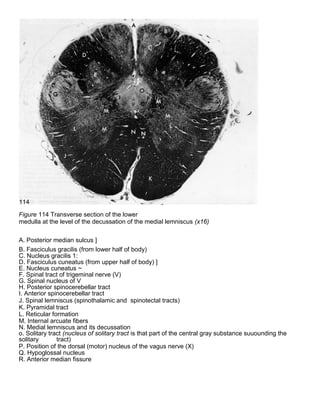

Figure 114 Transverse section of the lower

medulla at the level of the decussation of the medial lemniscus (x16)

A. Posterior median sulcus ]

B. Fasciculus gracilis (from lower half of body)

C. Nucleus gracilis 1:

D. Fasciculus cuneatus (from upper half of body) ]

E. Nucleus cuneatus ~

F. Spinal tract of trigeminal nerve (V)

G. Spinal nucleus of V

H. Posterior spinocerebellar tract

I. Anterior spinocerebellar tract

J. Spinal lemniscus (spinothalamic and spinotectal tracts)

K. Pyramidal tract

L. Reticular formation

M. Internal arcuate fibers

N. Medial lemniscus and its decussation

o. Solitary tract (nucleus of solitary tract is that part of the central gray substance suuounding the

solitary tract)

P. Position of the dorsal (motor) nucleus of the vagus nerve (X)

Q. Hypoglossal nucleus

R. Anterior median fissure

Figure 114 Transversesection of the lower medulla at the level of the decussation of the medial lemniscus (x16) A. Posterior median sulcus ] B. Fasciculus gracilis (from lower half of body) C. Nucleus gracilis 1: D. Fasciculus cuneatus (from upper half of body) ] E. Nucleus cuneatus ~ F. Spinal tract of trigeminal nerve (V) G. Spinal nucleus of V H. Posterior spinocerebellar tract I. Anterior spinocerebellar tract J. Spinal lemniscus (spinothalamic and spinotectal tracts) K. Pyramidal tract L. Reticular formation M. Internal arcuate fibers N. Medial lemniscus and its decussation o. Solitary tract (nucleus of solitary tract is that part of the central gray substance suuounding the solitary tract) P. Position of the dorsal (motor) nucleus of the vagus nerve (X) Q. Hypoglossal nucleus R. Anterior median fissure